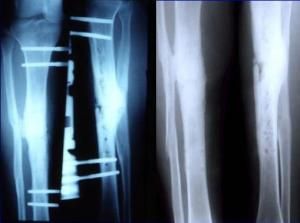

骨不連X線圖片在確定骨不連的治療時,必須考慮以下因素:明確原因,骨不連的部位(具體的骨及骨內的位置),骨 不連的類型,之前的治療,X線表現,以及一系列其他病人的具體特點。在廣義上,治療計畫應包括改善局部生物學行為或/和加強其機械穩定性。常用的改善局部生物性狀的治療方法包括:去除感染灶,骨移植,骨髓移植和套用Ilizarov方法。提高機械穩定性的方法包括:鋼板螺釘內固定術,髓內釘內固定和外固定架。